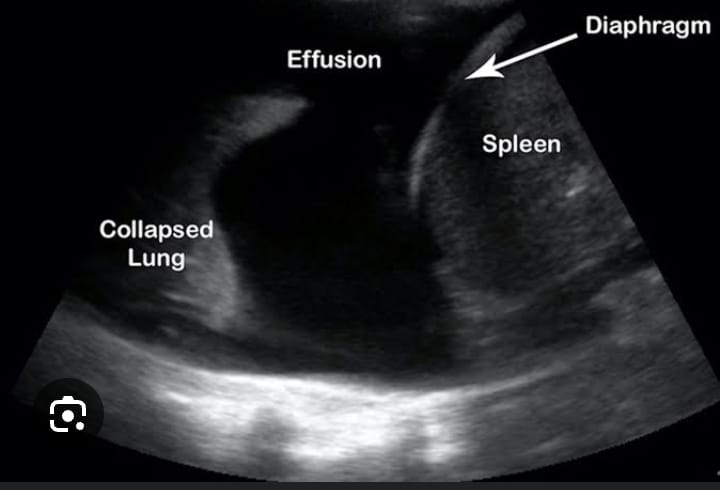

12.CHEST(LUNG) ULTRASOUND

Topics Covered: Basics of ultrasound, Scanning Techniques for Chest, Interpretation of Normal Lung Anatomy, Diagnosing Lung pathologies…..

13.EMERGENCY ULTRASOUND

Basic Physics, scanning protocols, FAST scan, E-FAST scans, abdominal traumas, Fluid patterns, Hematomas, Diaphragm, Pneumothorax, Endotracheal Intubation.